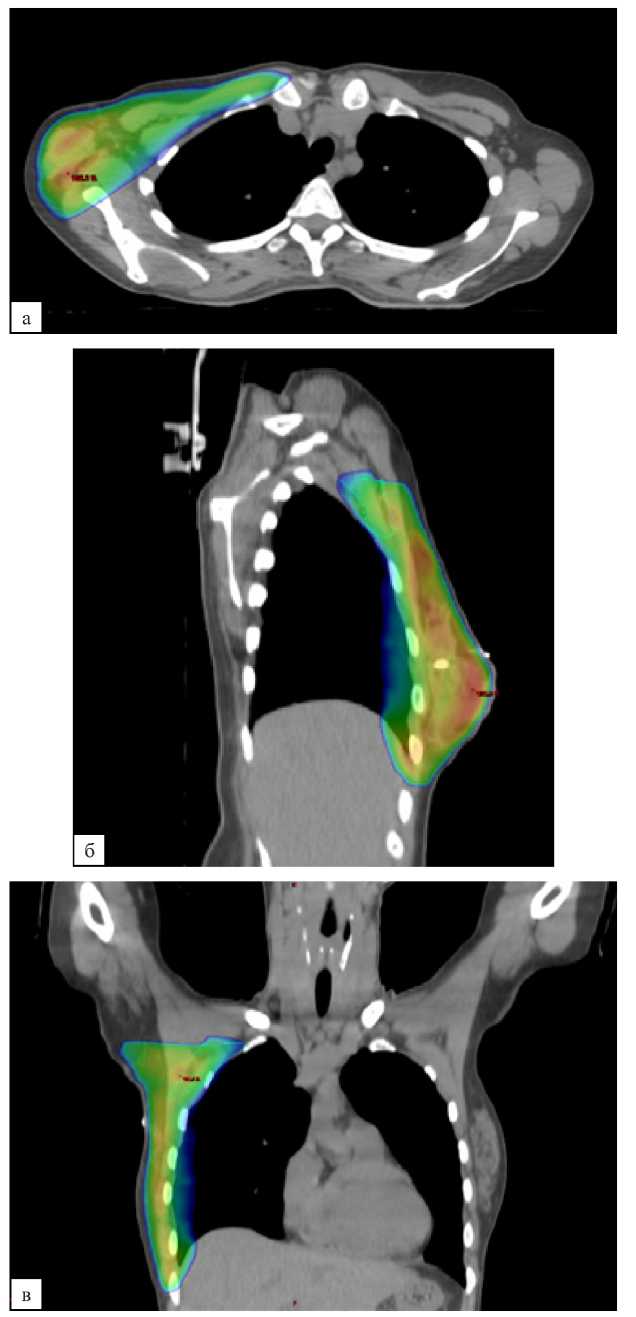

В контрольной группе послеоперационная лучевая терапия проводилась в стандартном объеме — облучение оставшихся тканей молочной железы (после органосохраняющего лечения) или мягких тканей передней грудной стенки (после мастэктомии) с подмышечными ЛУ I, II, III уровней и надключичными ЛУ (рис. 2, а, б, в). При планировании объемов облучения в исследуемой группе из объема облучения исключались подмышечные ЛУ III уровня и надключичные ЛУ (рис. 3, а, б, в). Оконтуривание всех указанных структур выполнялось согласно рекомендациям ESTRO от 2015 года [15].

Рис. 3 (а, б, в). Дозиметрический план лучевой терапии молочной железы и подмышечных лимфатических узлов I, II уровней. а — аксиальная проекция; б — сагиттальная проекция; в — фронтальная проекция

Fig. 3 (а, б, в). Dosimetric plan for the breast RT, axillary lymph nodes of levels I, II. a — axial plane; б — sagittal plane; в — frontal plane